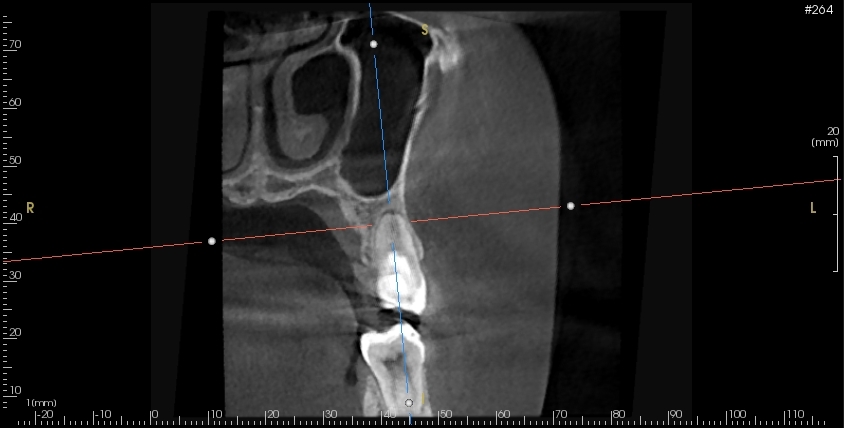

まず再生歯内療法(REGENERATIVE ENDODONTICS)とは、何かというと歯髄壊死と診断された根未完成の歯に行われる治療です。

この治療の目的は歯髄象牙質複合体を再生し、歯の寿命を伸ばし、正常な機能を回復することです。

この治療は根未完成歯に限られますが、失活した根未完成歯に対して、神経を全て除去することなく正常な機能に戻すことができる可能性がある治療です。